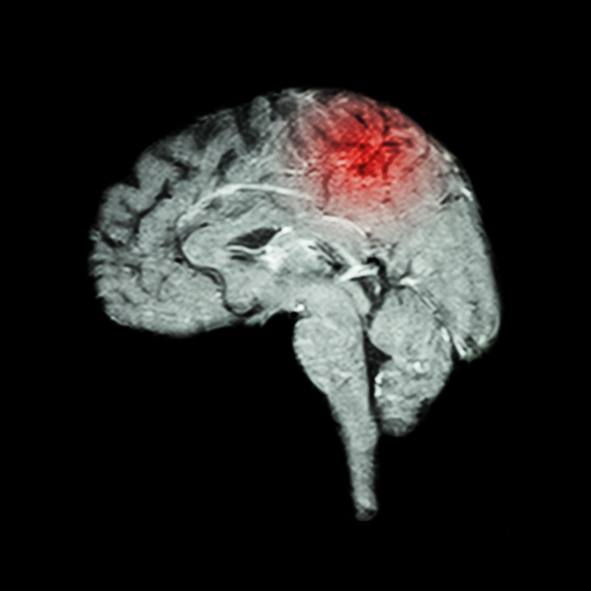

A hypertensive crisis is a quick and severe risk in blood pressure that can lead to a stroke. Extremely high blood pressure refers to readings of 180/120 mm Hg and higher and it can cause damage to the blood vessels. When blood pressure is this high, the heart is unable to pump blood efficiently. For ...click here to read more